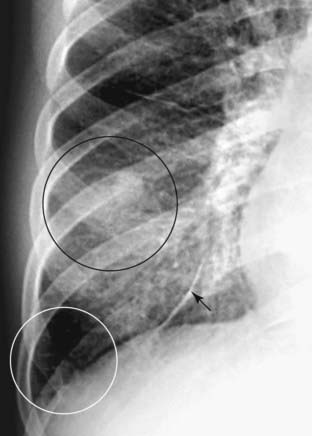

Figure 3-4 Silhouette sign, right middle lobe pneumonia.

A, Fluffy, indistinctly marginated airspace disease is seen to the right of the heart. It obscures the right heart border (solid black arrow) but not the right hemidiaphragm (dotted black arrow). This is called the silhouette sign and establishes that the disease (1) is in contact with the right heart border (which lies anteriorly in the chest) and (2) is the same radiographic density as the heart (fluid or soft tissue). Pneumonia fills the airspaces with an inflammatory exudate of fluid density. B, The area of the consolidation is indeed anterior, located in the right middle lobe, which is bound by the major fissure below (dotted white arrow) and the minor fissure above (solid white arrow).